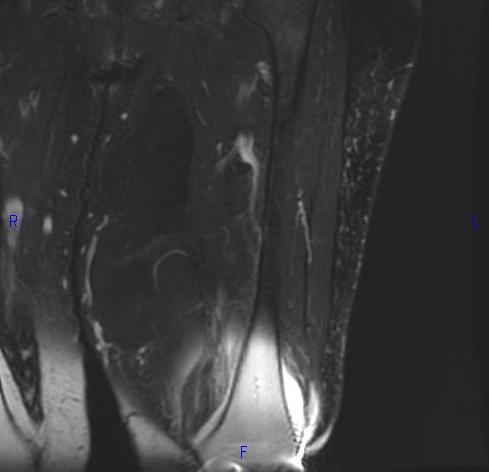

MRI (Fig. 1, 2, 3 and 4)

• Large encapsulated lipomatous mass. (Fig. 1, 2, 3 and 4)

• Greater than 75% adipose tissue (Hyperintense on T1-weighted) (Fig. 1)

• Nonadipose components; prominent thick septa and focal nodular regions usually less than 2 cm in size. (Fig. 3)

• Loss of signal on fat-saturated T1-weighted images.

• MRI does not appear homogeneous. (Fig. 4)

• High signal on T1 and low signal on T2 fat suppressed

• Fibrous stranding typical

Fig. 2-4 MRI: Coronal T2-weighted fat suppressed (Fig. 2) and Axial T2-weighted FS (Fig. 3) shows low intensity signal isointense with fat. Adypocitic lesion with fatty signal is located in the posterior and medial compartment of the thigh. Thickened septa and nodularity enhances on post contrast images. (Fig. 4)